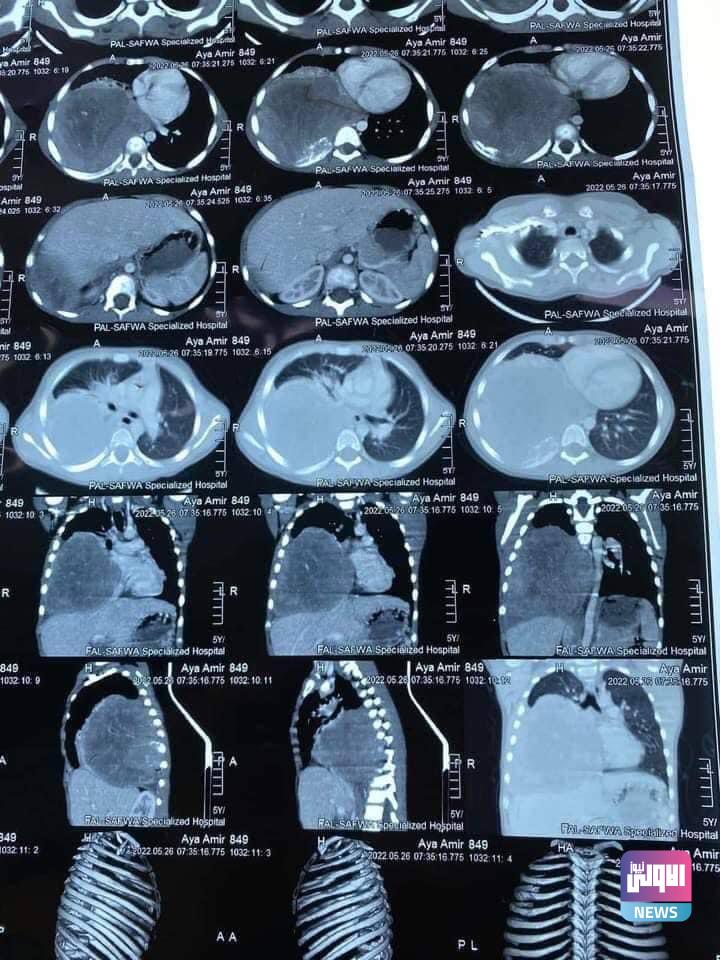

نجح فريق جراحي متخصص بجراحة الصدر والأوعية الدموية في مستشفى الرمادي التعليمي التابع لدائرة صحة الأنبار يإجراء عملية استئصال ورم من طفلة مريضة بعمر 6 سنوات

وذكر رئيس الفريق الجراحي الدكتور بشار برجس اختصاص جراحة الصدر والاوعية الدموية ان الطفلة كانت تعاني من وجود ورم في التجويف الصدري الملتصق بشخاف القلب والرئة والحجاب الحاجز .

مؤكدآ ان عملية استئصال الورم بالكامل وتكللت بالنجاح التام والطفلة بصحة جيدة بجهود الفريق الطبي والجراحي والتمريضي الساند.